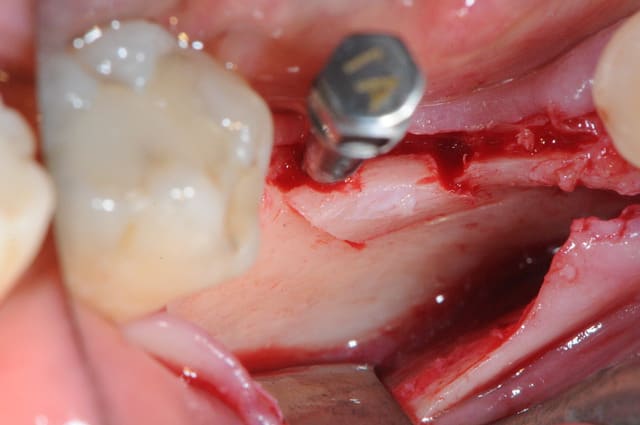

tiens pour faire avancer le débat un cas de ROG verticale et horizontale, avec membrane PTFE armé titane.

à la mandibule, non je n'ai pas fait de photos avec la membrane, trop compliqué dans ce cas là, surtout pour ce qu'en fait, j'ai mis un mélange bio-oss autogéne à 50/50 le tout recouvert par un bio-gide securisée par des pin's.